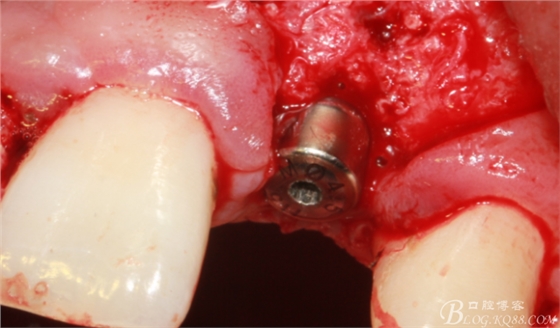

刮自體骨覆蓋種植體表面。

血液調(diào)扮BIO-OSS骨粉覆蓋術(shù)區(qū)。

蓋生物膜,固定。

減張縫合。自我感覺一切OK。囑其近期不可劇烈活動(dòng),也不要總想著為國足報(bào)仇。